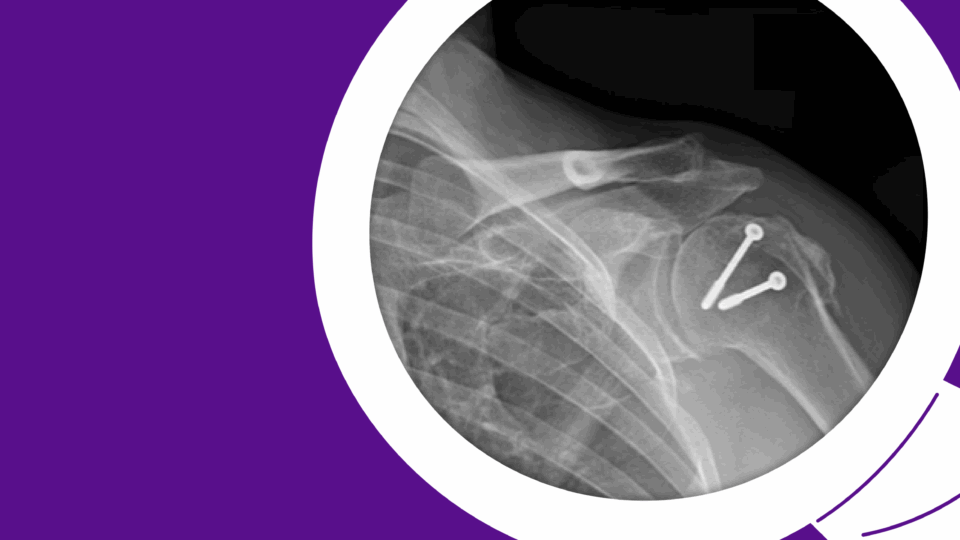

Complex Case Spotlight

Osseointegration Surgery Improves Connection Between Limb & Prosthesis